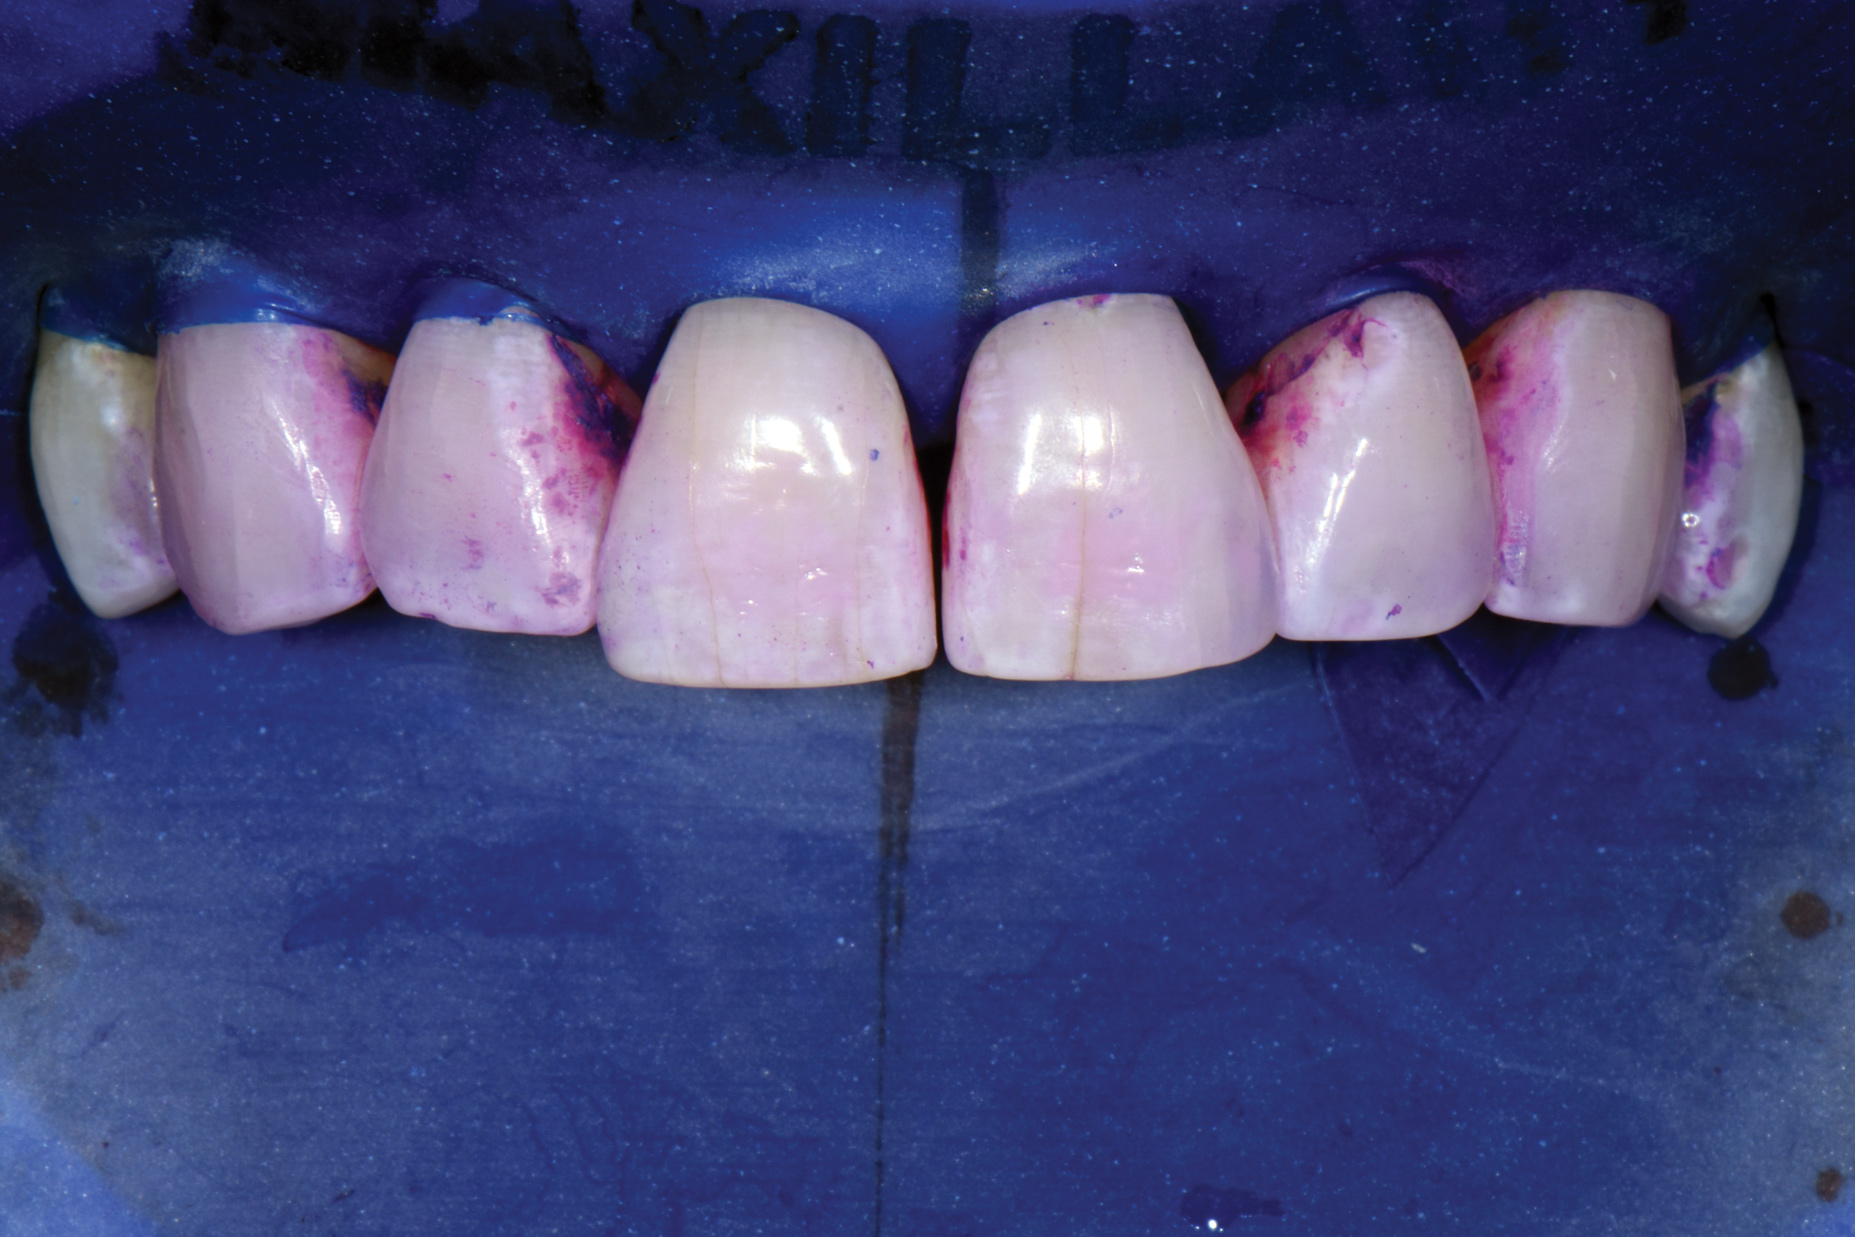

Biofilm Removal

Air abrasion with aluminum trihydroxide has been used as an adjunctive for tooth preparation to remove plaque, light calculus, undermined enamel, poorly bonded resins or liners, and soft-tissue tags prior to bonding. The rationale of biofilm removal before bonding is to remove any impediments to effective etching of enamel that may lead to reduced bond strength and microgaps that could contribute to future stain and leakage. Because biofilm can be difficult to visualize, a one-time application of a two-tone disclosing solution to dried teeth may help reveal biofilm and provide a visual cue for effective removal (Figure 17 through Figure 19). Some cleaning particles other than glycine or sodium bicarbonate can alter the enamel surface; therefore, reapplication of disclosing solution should be avoided as this may lead to risk of undesired staining of tooth structure.

Fig 17. Application of two-tone disclosing solution to reveal biofilm.

Figure 17

Fig 18. Air abrasion with aluminum trihydroxide to remove biofilm.

Figure 18

Fig 19. Cleaned tooth surfaces after air abrasion prior to application of adhesive bonding resin composite to close black triangles.

Figure 19